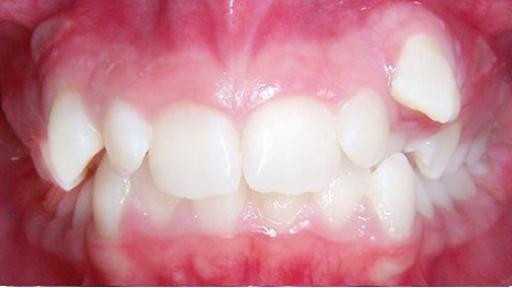

Установка керамических брекетов

Пациентка обратилась с жалобой на неправильное положение верхнего клыка. Были установлены керамические брекеты, срок ношения 11 месяцев. В результате ортодонтического лечения был успешно исправлен прикус и расширены зубные ряды.

Доктор: Хачатрян Лариса Рубеновна